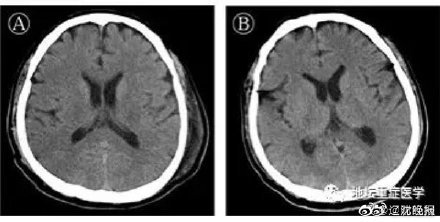

【北京地坛医院首证新冠病毒进犯中枢神经系统,主张完善脑脊液检测】脑脊液中存在新冠病毒 北京地坛医院4日发布,此前的2月25日,首例新冠肺炎兼并脑炎患者从该院顺畅出院。该院ICU主任刘景院提示:患者呈现认识妨碍,一定要考虑病毒有或许进犯中枢神经系统。现在来说,新冠肺炎患者可兼并重度呼吸困顿综合征(ARDS)、心肌危害、凝血功用反常、肾脏危害、肝脏危害等多脏器危害,但没有发现有中枢神经系统劳累的报导,此病例报导在全球尚属首例。医治团队在对该患者脑脊液标本进行宏基因组二代测序、判定或许的感染病原体过程中,排除了其他病原体,获得了新冠病毒基因组序列。经过基因测序证明脑脊液中存在新冠病毒,临床确诊病毒性脑炎。刘景院提示,在临床调查中,不乏有颈反抗,病理征阳性,突发认识妨碍乃至昏倒的病例存在,面临此类患者,需求警觉新冠病毒感染可累及中枢神经系统,及时进行脑脊液等相关查看,并完善脑脊液SARS-CoV-2核酸及基因测序等作业,为更全面了解COVID-19做出探究,并活跃处理相关神经系统并发症,然后进一步下降危重患者的病死率。@汹涌新闻 北京地坛医院首证新冠进犯中枢神经系统,主张完善脑脊液检测汹涌新闻